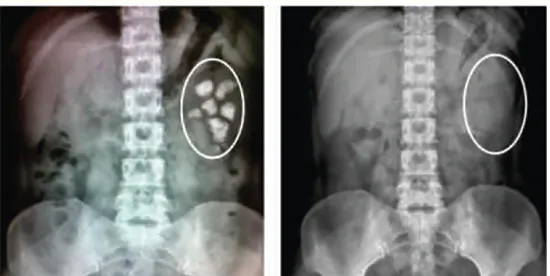

Ảnh minh họa

Sỏi thận, sỏi mật = Quả bom nổ chậm

Sau khi sỏi hình thành, to dần, nhiều dần, dẫn đến viêm đường tiết niệu, đến giai đoạn cuối làm hoại tử thận, xơ gan và biến chứng, đây là quá trình phát triển dần của bệnh, không nhất thiết phải phẫu thuật, tán sỏi, nên dùng thuốc điều trị triệt để kịp thời.